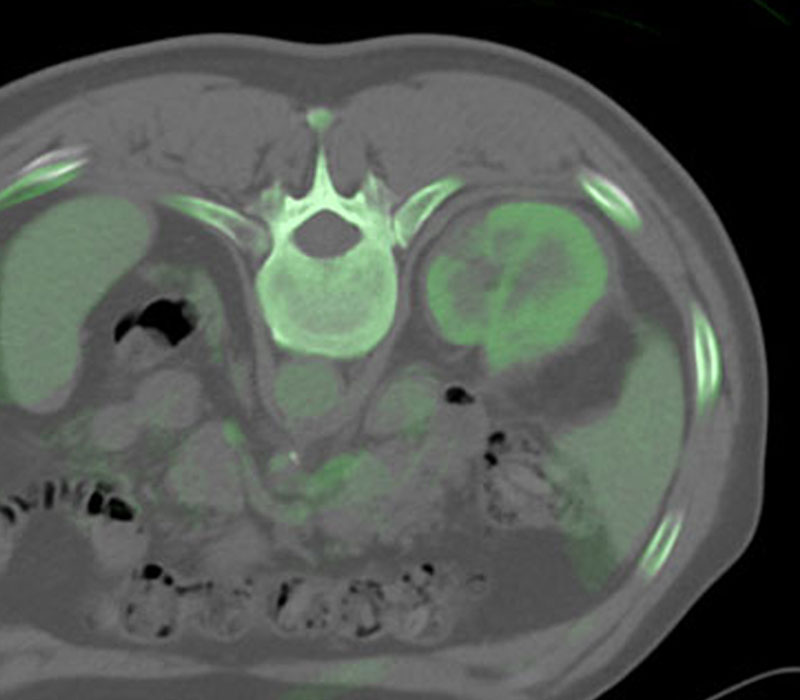

IGTFusion used to guide and confirm accurate needle placement in 3 renal lesions that were not visible on CT during the procedure.

- Registered a supine pre-procedural image to a prone procedural image

- Saved procedure time by eliminating the need to constantly refer back to the pre-procedural image